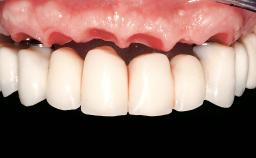

Immediate Loading of Eight Implants in the Maxilla and Six Implants in the Mandible and Final Restoration with Three-Unit and Four-Unit FDPs

Extensive scientific evidence has confirmed that immediately loaded implants with fixed full-arch provisional restorations can osseointegrate with success rates similar to conventionally or delayed loaded implants. A number of immediate-provisionalization techniques for edentulous jaws have been described. Some protocols differ when it comes to prefabricated provisional templates versus complete denture conversion; intrasurgical impressions versus direct relining; and cemented versus screw-retained provisional restorations. In this context, complete-denture conversion has been proposed for either intrasurgical impressions or direct relining. Another possibility is the utilization of a prefabricated provisional to be adapted either in the mouth (by direct relining) or in the laboratory (on a working model obtained from an intrasurgical impression).

Prosthesis Type FDP

Defining Characteristics Fully edentulous upper jaw to be rehabilitated with an implant-borne fixed dental prosthesis

Loading Protocol Immediate